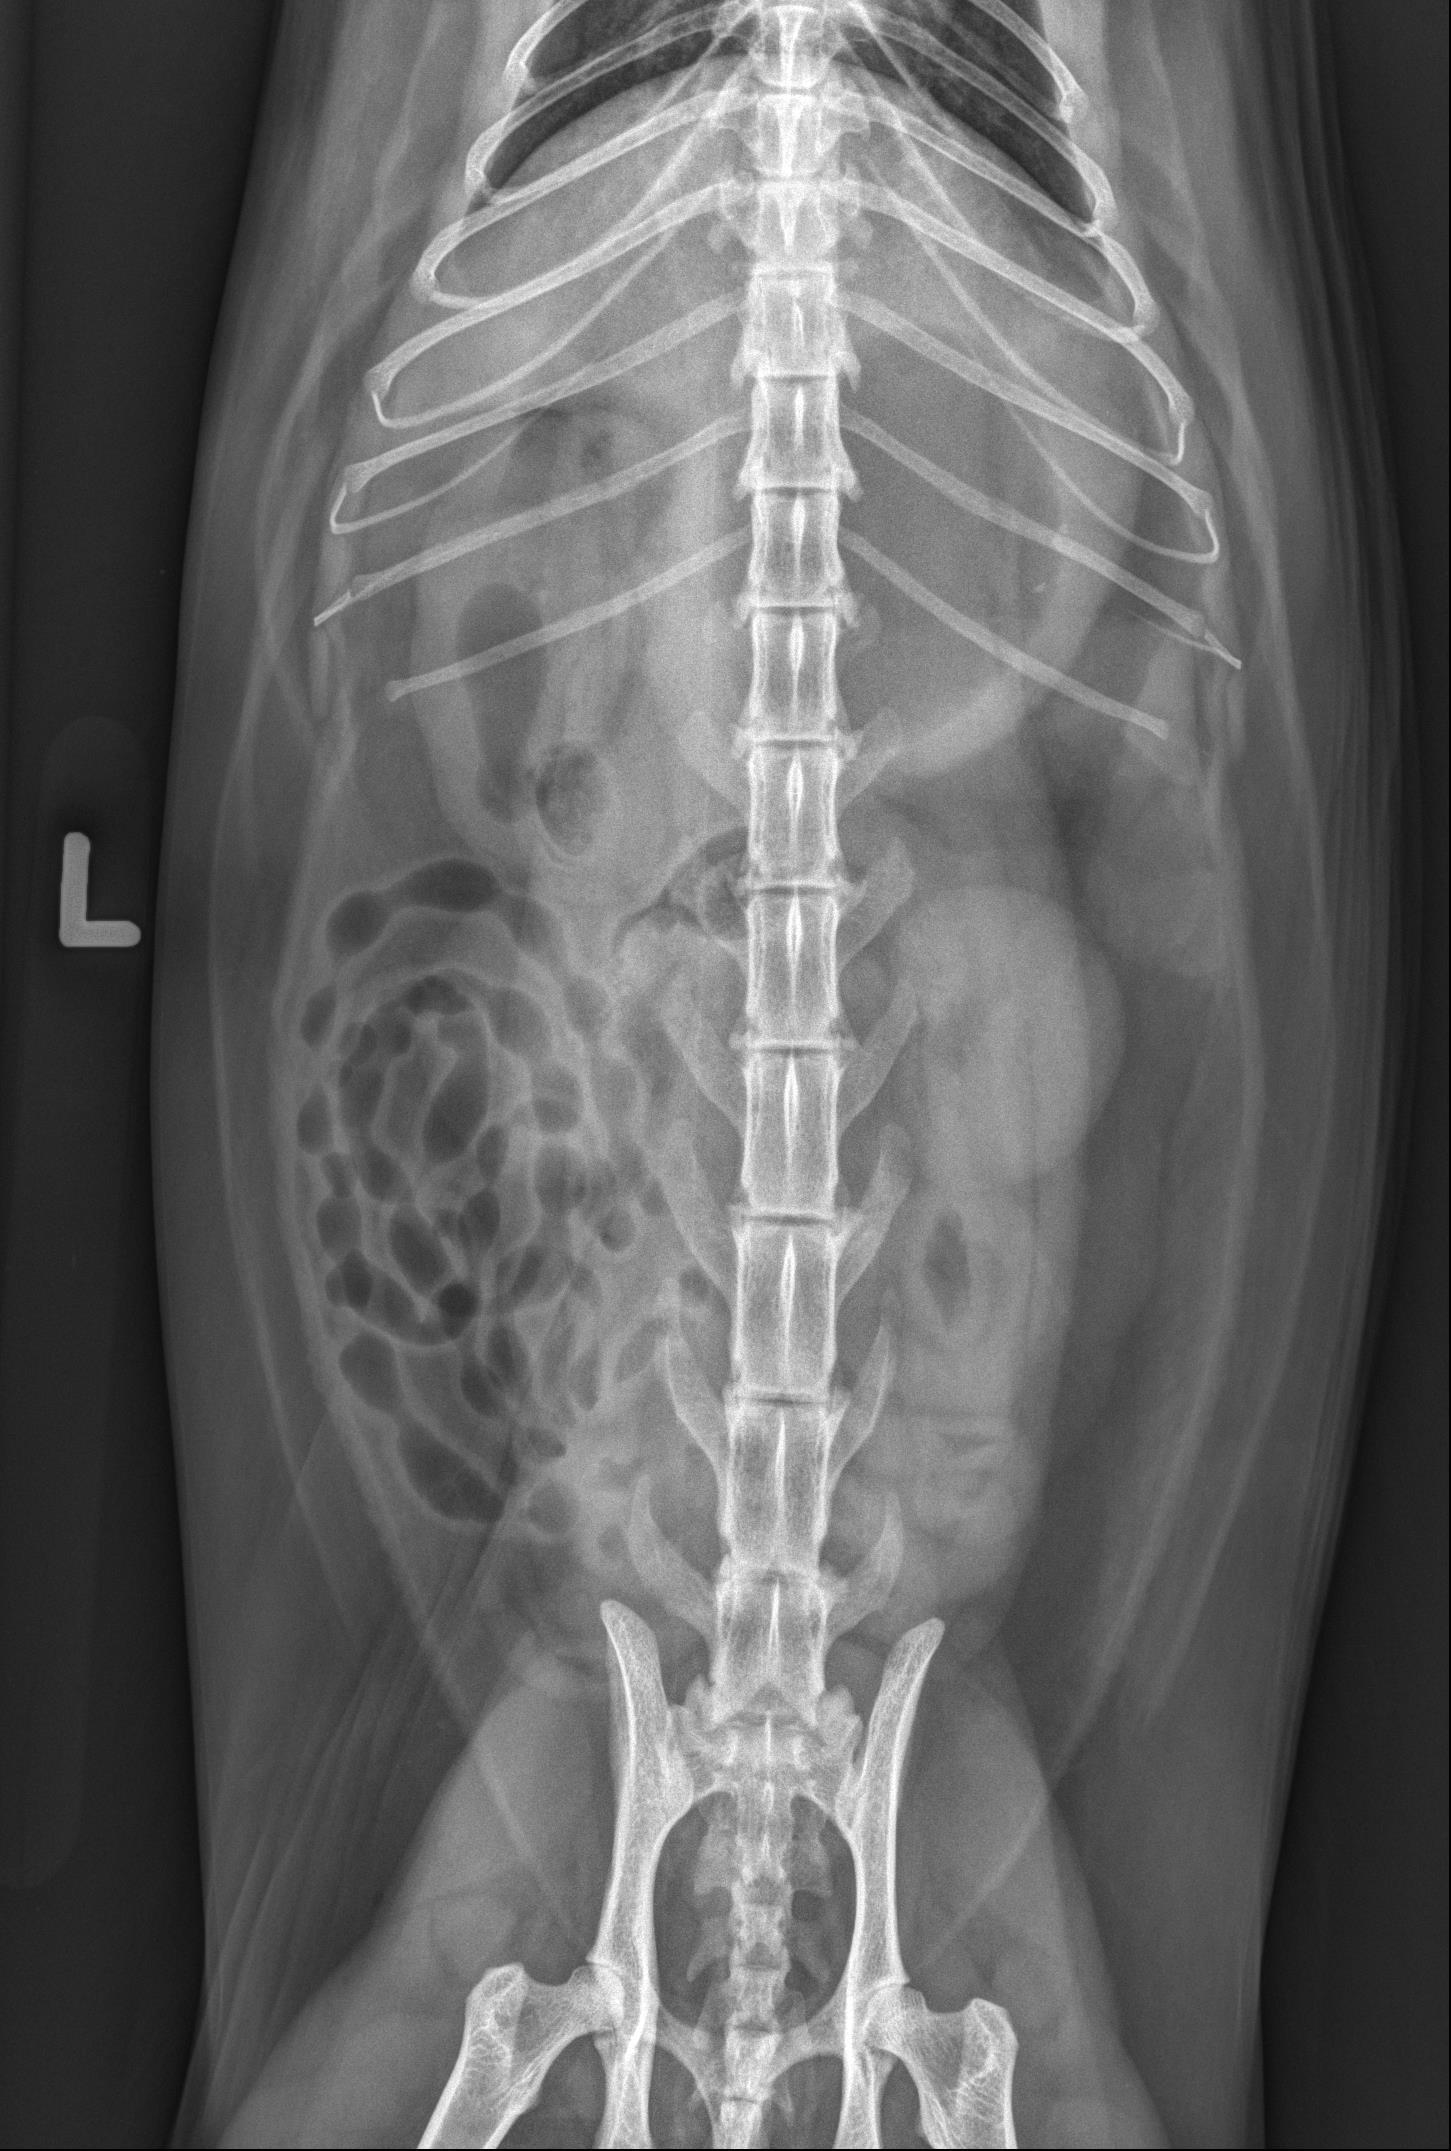

Study: Left lateral, right lateral, and ventrodorsal abdominal radiographs are available for review.

Findings: The stomach is distended with a large volume of fluid, a smaller volume of gas, and a small number of pinpoint, mineral opaque foci. In the orad duodenum, seen ventral to the last pair of ribs in the lateral views and to the right of L2 in the ventrodorsal view, there is an ovoid structure in the duodenal lumen. The structure is gas-filled with a soft tissue opaque border surrounded by a thin rim of gas. It measures approximately 2 cm in length and 1 cm in diameter. The duodenum orad to this structure is mildly distended while the duodenum aborad to this structure appears empty/small in diameter. The remainder of the small intestinal tract is mildly, uniformly distended with fluid and gas in a string of pearls pattern, consistent with peristalsis. The colon contains a small volume of nonformed stool. The serosal detail, liver, spleen, kidneys, retroperitoneal space, and urinary bladder are normal. The imaged skeletal structures and caudal thorax are unremarkable.

Conclusions: Ovoid structure (suspected gas-filled foreign body) in the orad duodenum causing intestinal obstruction. Surgical intervention is warranted.